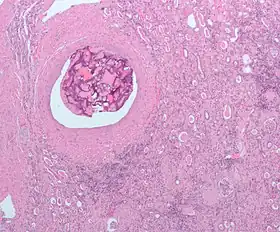

![]() Micrograph of embolic material in the artery of a kidney. The kidney was surgically removed because of cancer. H&E stain. |